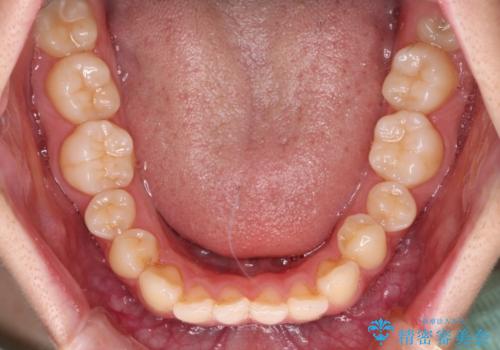

- ハーフリンガル

上下前歯が嘴のように前方に突出しており、唇が閉じにくい状態であったため、上下左右の第一小臼歯4本を抜歯して、口元の突出感を改善することとしました。

口元の印象が劇的に解消され、気にしていたガミースマイルも図らずも改善することができました。